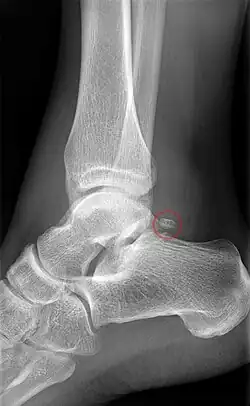

Os trigonum

The os trigonum or accessory talus represents a failure of fusion of the lateral tubercle of the posterior process of the talus bone. Is estimated to be present in 7–25% of adults.[17] It can be mistaken for an avulsion fracture of lateral tubercle of talus (Shepherd fracture) or a fracture of the Stieda process. In most cases, Os Trigonum will go unnoticed, but with some ankle injuries it can get trapped between the heel and ankle bones which irritates the surrounding structures, leading to Os Trigonum Syndrome.[21]